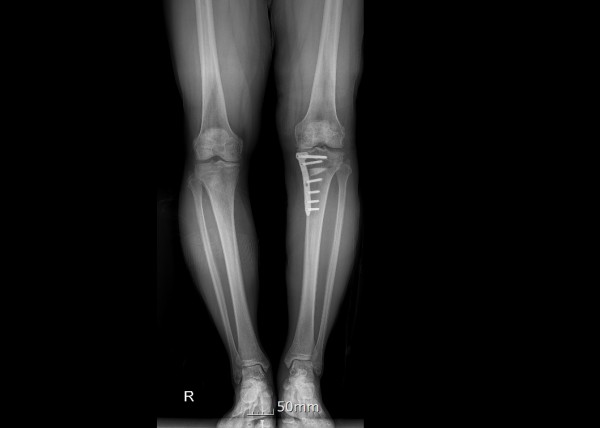

무릎 관절의 통증과 기능 장애는 전 세계 수백만 명의 사람들이 겪고 있는 공통된 건강 문제입니다. 이러한 문제를 해결하기 위한 의학적 접근법 중에서도, 절골수술과 연골재생은 주목할 만한 치료 방법으로 부상하고 있습니다. 이 두 가지 방법은 무릎 관절의 기능을 개선하고, 통증을 줄이며, 환자의 삶의 질을 향상시키는 데 목적을 두고 있습니다.

절골수술은 무릎 관절의 비정상적인 정렬을 교정하기 위한 수술적 방법입니다. 이 수술은 주로 관절염으로 인한 통증과 기능 장애를 겪고 있는 환자들에게 시행됩니다. 수술 과정에서는 뼈를 절단하고 재정렬하여 무릎에 가해지는 압력을 분산시킴으로써, 관절에 대한 스트레스를 줄이고 통증을 완화시킵니다. 이러한 접근법은 관절의 수명을 연장시키고, 궁극적으로는 관절 교체 수술을 피할 수 있게 해줍니다.